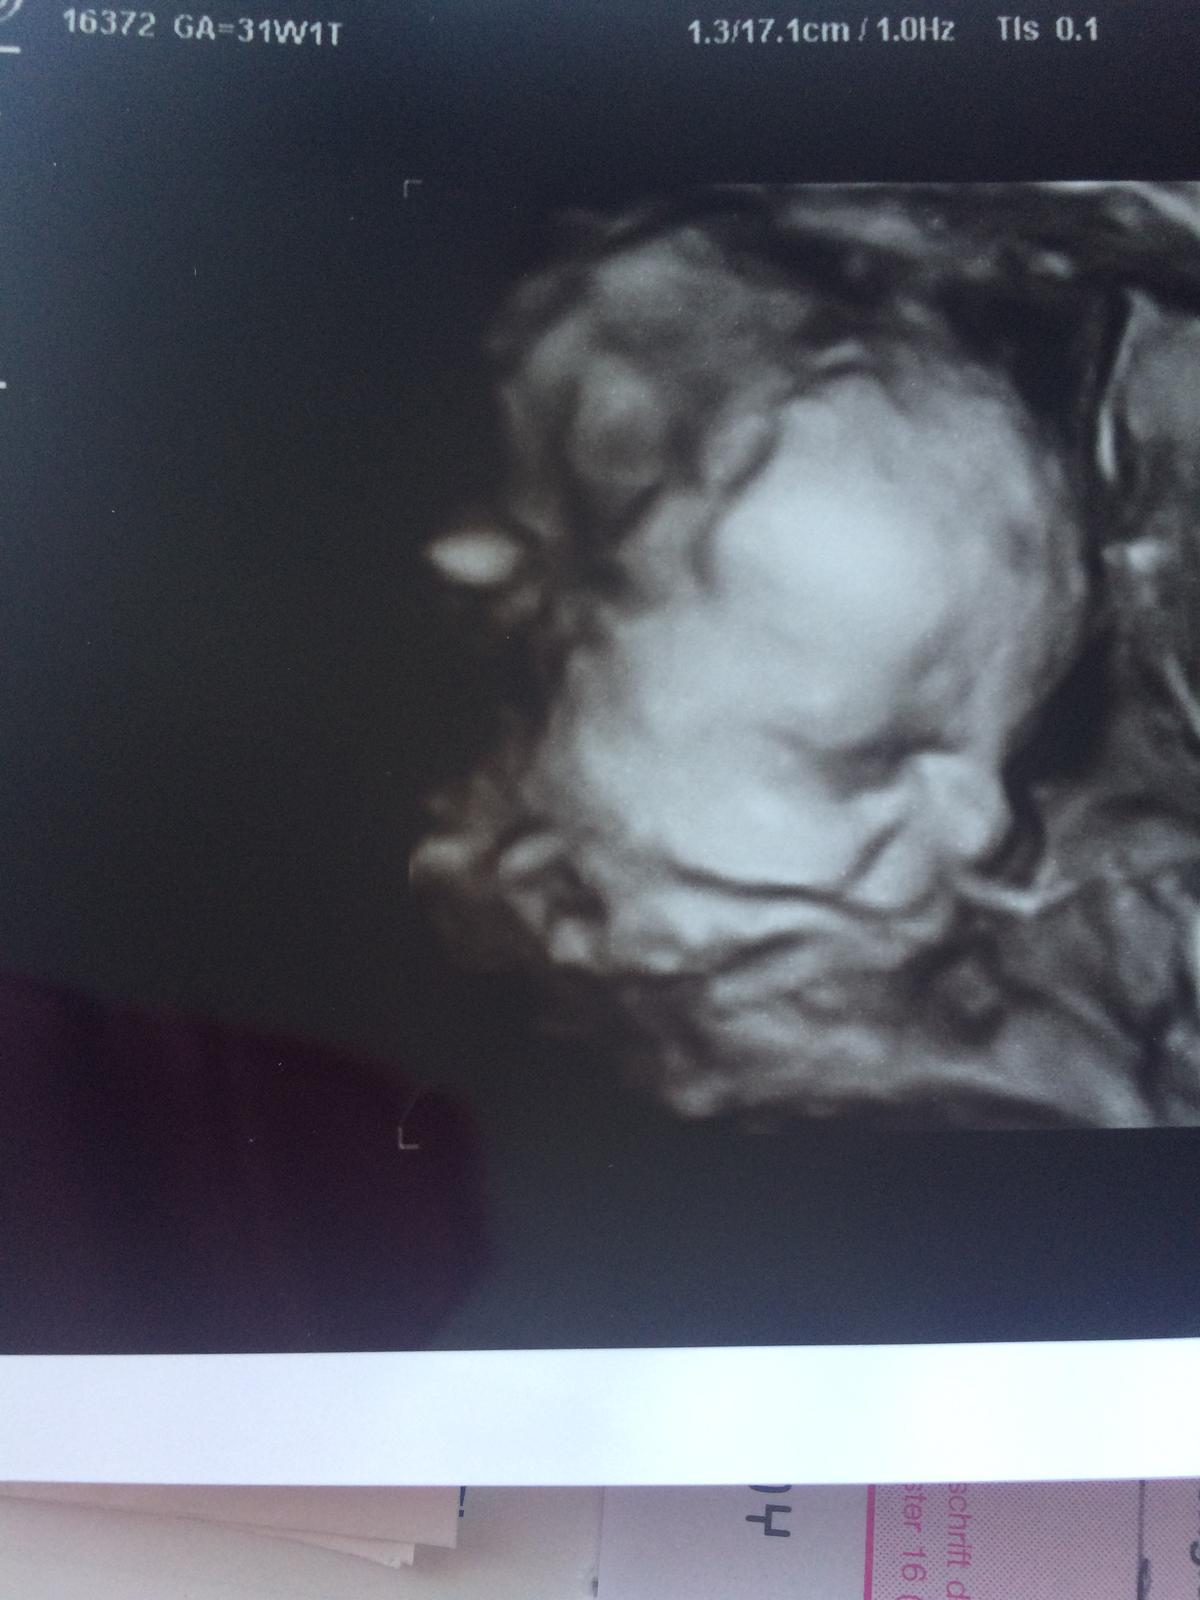

@blondie257 Lekár mi nepovedal že zcoho ma bolia tie rebra že môže byt z kašľa mala je v poriadku teraz som 31-1tt maká ma 2kg 42cm